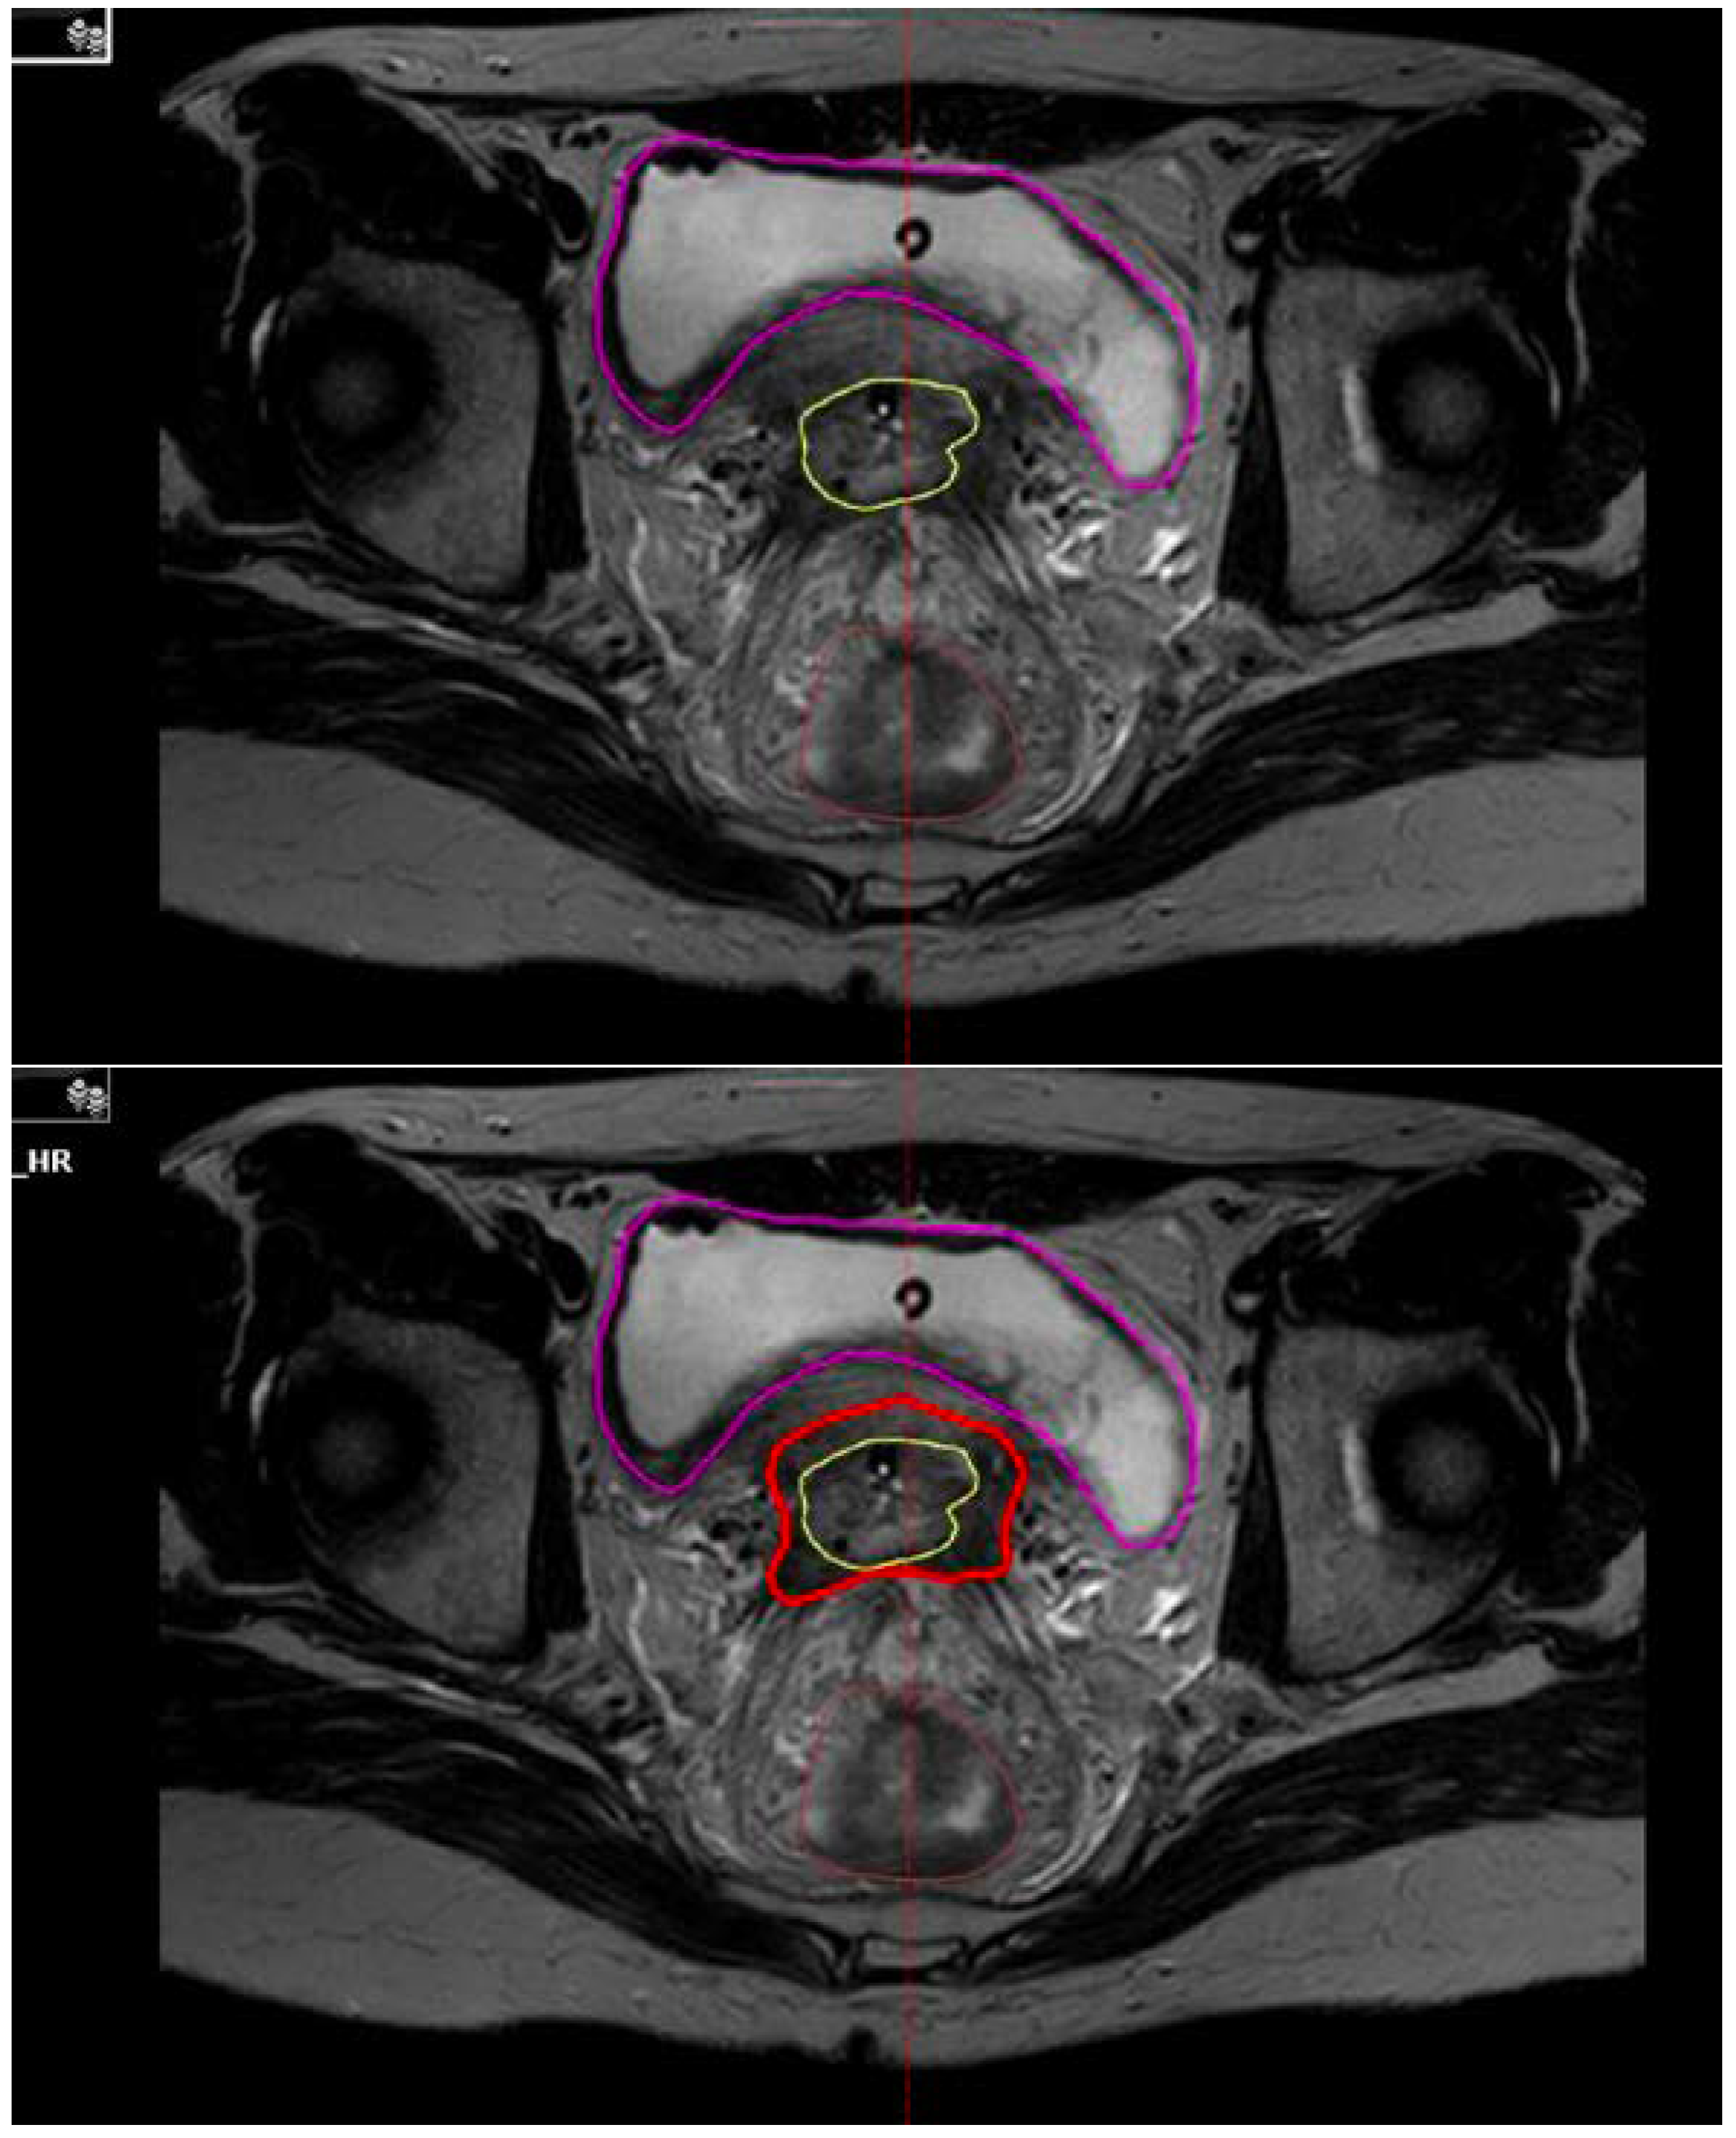

- Haie-Meder, C.; Pötter, R.; Van Limbergen, E.; Briot, E.; De Brabandere, M.; Dimopoulos, J.; Dumas, I.; Hellebust, T.P.; Kirisits, C.; Lang, S. Recommendations from Gynaecological (GYN) GEC-ESTRO Working Group(I): Concepts and terms in 3D image based 3D treatment planning in cervix cancer brachytherapy with emphasis on MRI assessment of GTV and CTV. Radiother. Oncol. 2005, 74, 235–245. [Google Scholar] [CrossRef]

- Pötter, R.; Haie-Meder, C.; Van Limbergen, E.; Barillot, I.; De Brabandere, M.; Dimopoulos, J.; Dumas, I.; Erickson, B.; Lang, S.; Nulens, A. Recommendations from gynaecological (GYN) GEC ESTRO working group (II): Concepts and terms in 3D image-based treatment planning in cervix cancer brachytherapy—3D dose volume parameters and aspects of 3D image-based anatomy, radiation physics, radiobiology. Radiother. Oncol. 2006, 78, 67–77. [Google Scholar] [CrossRef]

- Viswanathan, A.N.; Erickson, B.; Gaffney, D.K.; Beriwal, S.; Bhatia, S.K.; Burnett, O.L., III; D’Souza, D.P.; Patil, N.; Haddock, M.G.; Jhingran, A. Comparison and consensus guidelines for delineation of clinical target volume for CT-and MR-based brachytherapy in locally advanced cervical cancer. Int. J. Radiat. Oncol. Biol. Phys. 2014, 90, 320–328. [Google Scholar] [CrossRef] [PubMed]

- Image Guided Intensity Modulated External Beam Radiochemotherapy and MRI Based Adaptive Brachytherapy in Locally Advanced Cervical Cancer (EMBRACE-II) Study Protocol v.1.0. Rumpold. 2016. Available online: https://www.embracestudy.dk/UserUpload/PublicDocuments/EMBRACE%20II%20Protocol.pdf (accessed on 19 October 2021).